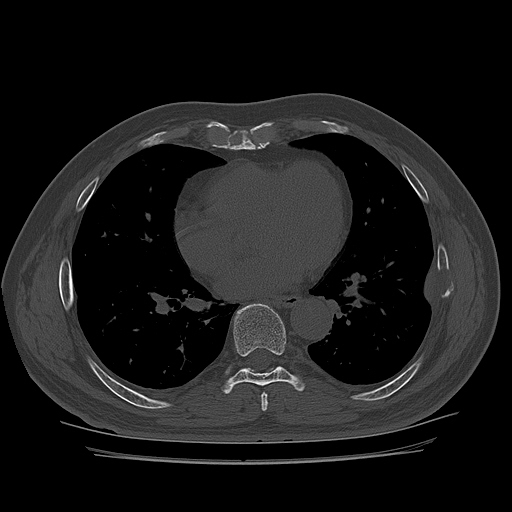

CT ; metastacic mass at rib and adjacent lung

CT image

1893637843_823ab0f0_CT162941144.jpg